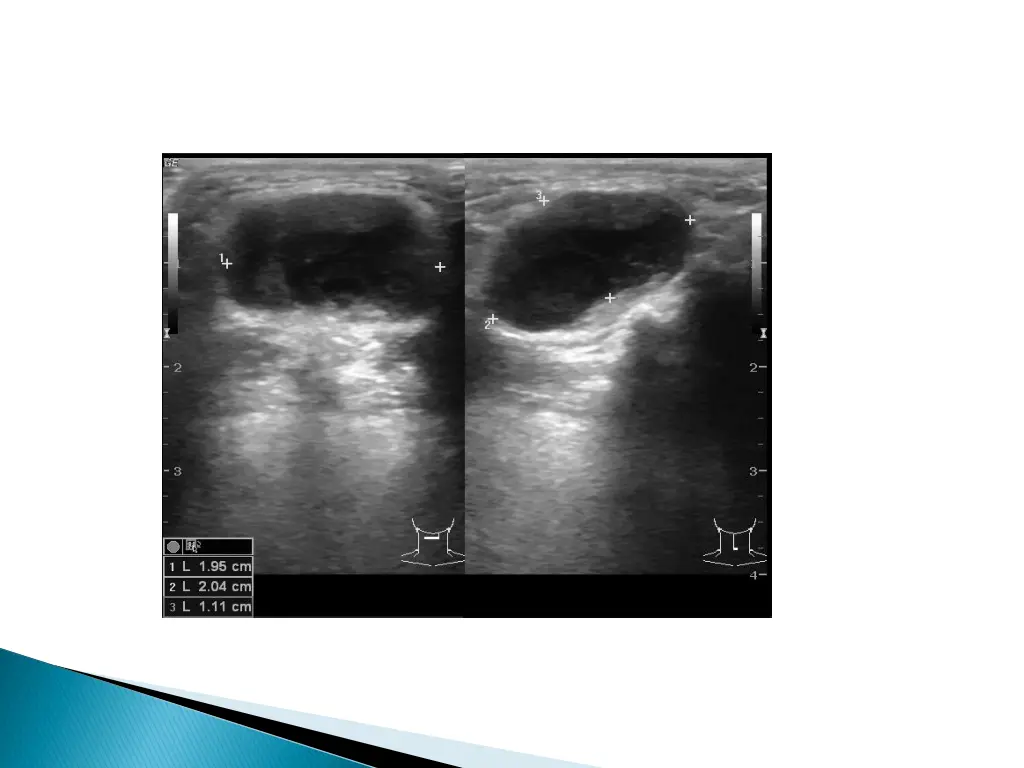

Usually the 1stinvestigation. Relationship to the surrounding structures. Confirms the cystic nature of lesion.

CHARACTERISTIC location : cyst like mass in the anterior neck in the midline at the level of hyoid bone or within the strap muscles. Anechoic mass in the characteristic location : CLASSIC APPEARANCE : less common. More common : hypoechoic lesion (homogenous/ heterogenous) with increased through transmission : with internal echos.

Presence/ absence of internal echos does not correlate with the pathological presence of inflammation. Mostly due to the presence of proteinaceous material within the cyst. Preoperative visualization of the normal thyroid tissue excludes the presence of ectopic thyroid tissue.